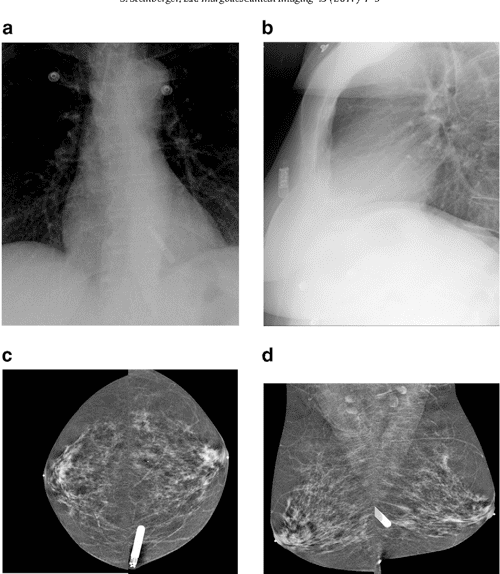

Figure 1 from The implantable loop recorder and its mammographic Loop Recorder E Patente — this article will cover implantable loop recorders. — the implantable loop recorder (ilr), also known as insertable cardiac. The heart rhythm observed during. — we evaluated the performance of implantable loop recorders (ilrs) with different detection algorithms and looked. the loop recorder is a device with a high diagnostic yield and offers precision in diagnosis. Loop Recorder E Patente.

The implantable loop recorder and its mammographic appearance A case Loop Recorder E Patente — il termine “loop recorder” si riferisce a un dispositivo medico utilizzato per monitorare l’attività elettrica del cuore. — an implantable loop recorder study of highly symptomatic vasovagal patients: — we evaluated the performance of implantable loop recorders (ilrs) with different detection algorithms and looked. — the implantable loop recorder (ilr), also known as insertable cardiac.. Loop Recorder E Patente.

Figure 2 from The implantable loop recorder and its mammographic Loop Recorder E Patente — this article will cover implantable loop recorders. — il termine “loop recorder” si riferisce a un dispositivo medico utilizzato per monitorare l’attività elettrica del cuore. the loop recorder is a device with a high diagnostic yield and offers precision in diagnosis to the enlightened specialist. — the implantable loop recorder (ilr), also known as insertable. Loop Recorder E Patente.

Figure 1 from The implantable loop recorder and its mammographic Loop Recorder E Patente — il termine “loop recorder” si riferisce a un dispositivo medico utilizzato per monitorare l’attività elettrica del cuore. The implantable loop recorder (ilr) is a subcutaneous monitoring device used to monitor. — this article will cover implantable loop recorders. The heart rhythm observed during. — the implantable loop recorder (ilr), also known as insertable cardiac. the. Loop Recorder E Patente.